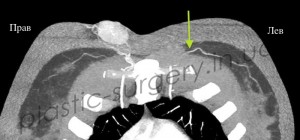

После предварительной локации точки выхода сосудов в покровные ткани в области поясницы, рядом с раневым дефектом с помощью аудио-допплера, больному было проведено более детальное обследование – КТ с ангиографией. При проведении исследования была визуализирована одна из люмбальных артерий и её перфорант справа от позвоночника, уточнено место выхода перфоранта, направление его оси и ветвление в покровных тканях (Рис. 3, 4, 5).

Рис. 3. Снимок компьютерной томографии с ангиографией, стрелкой отмечена люмбальная артерия. (слева).

Рис. 4. Снимок компьютерной томографии с ангиографией, стрелкой отмечена люмбальная артерия и её перфоранты, выходящие в покровные ткани. (справа).